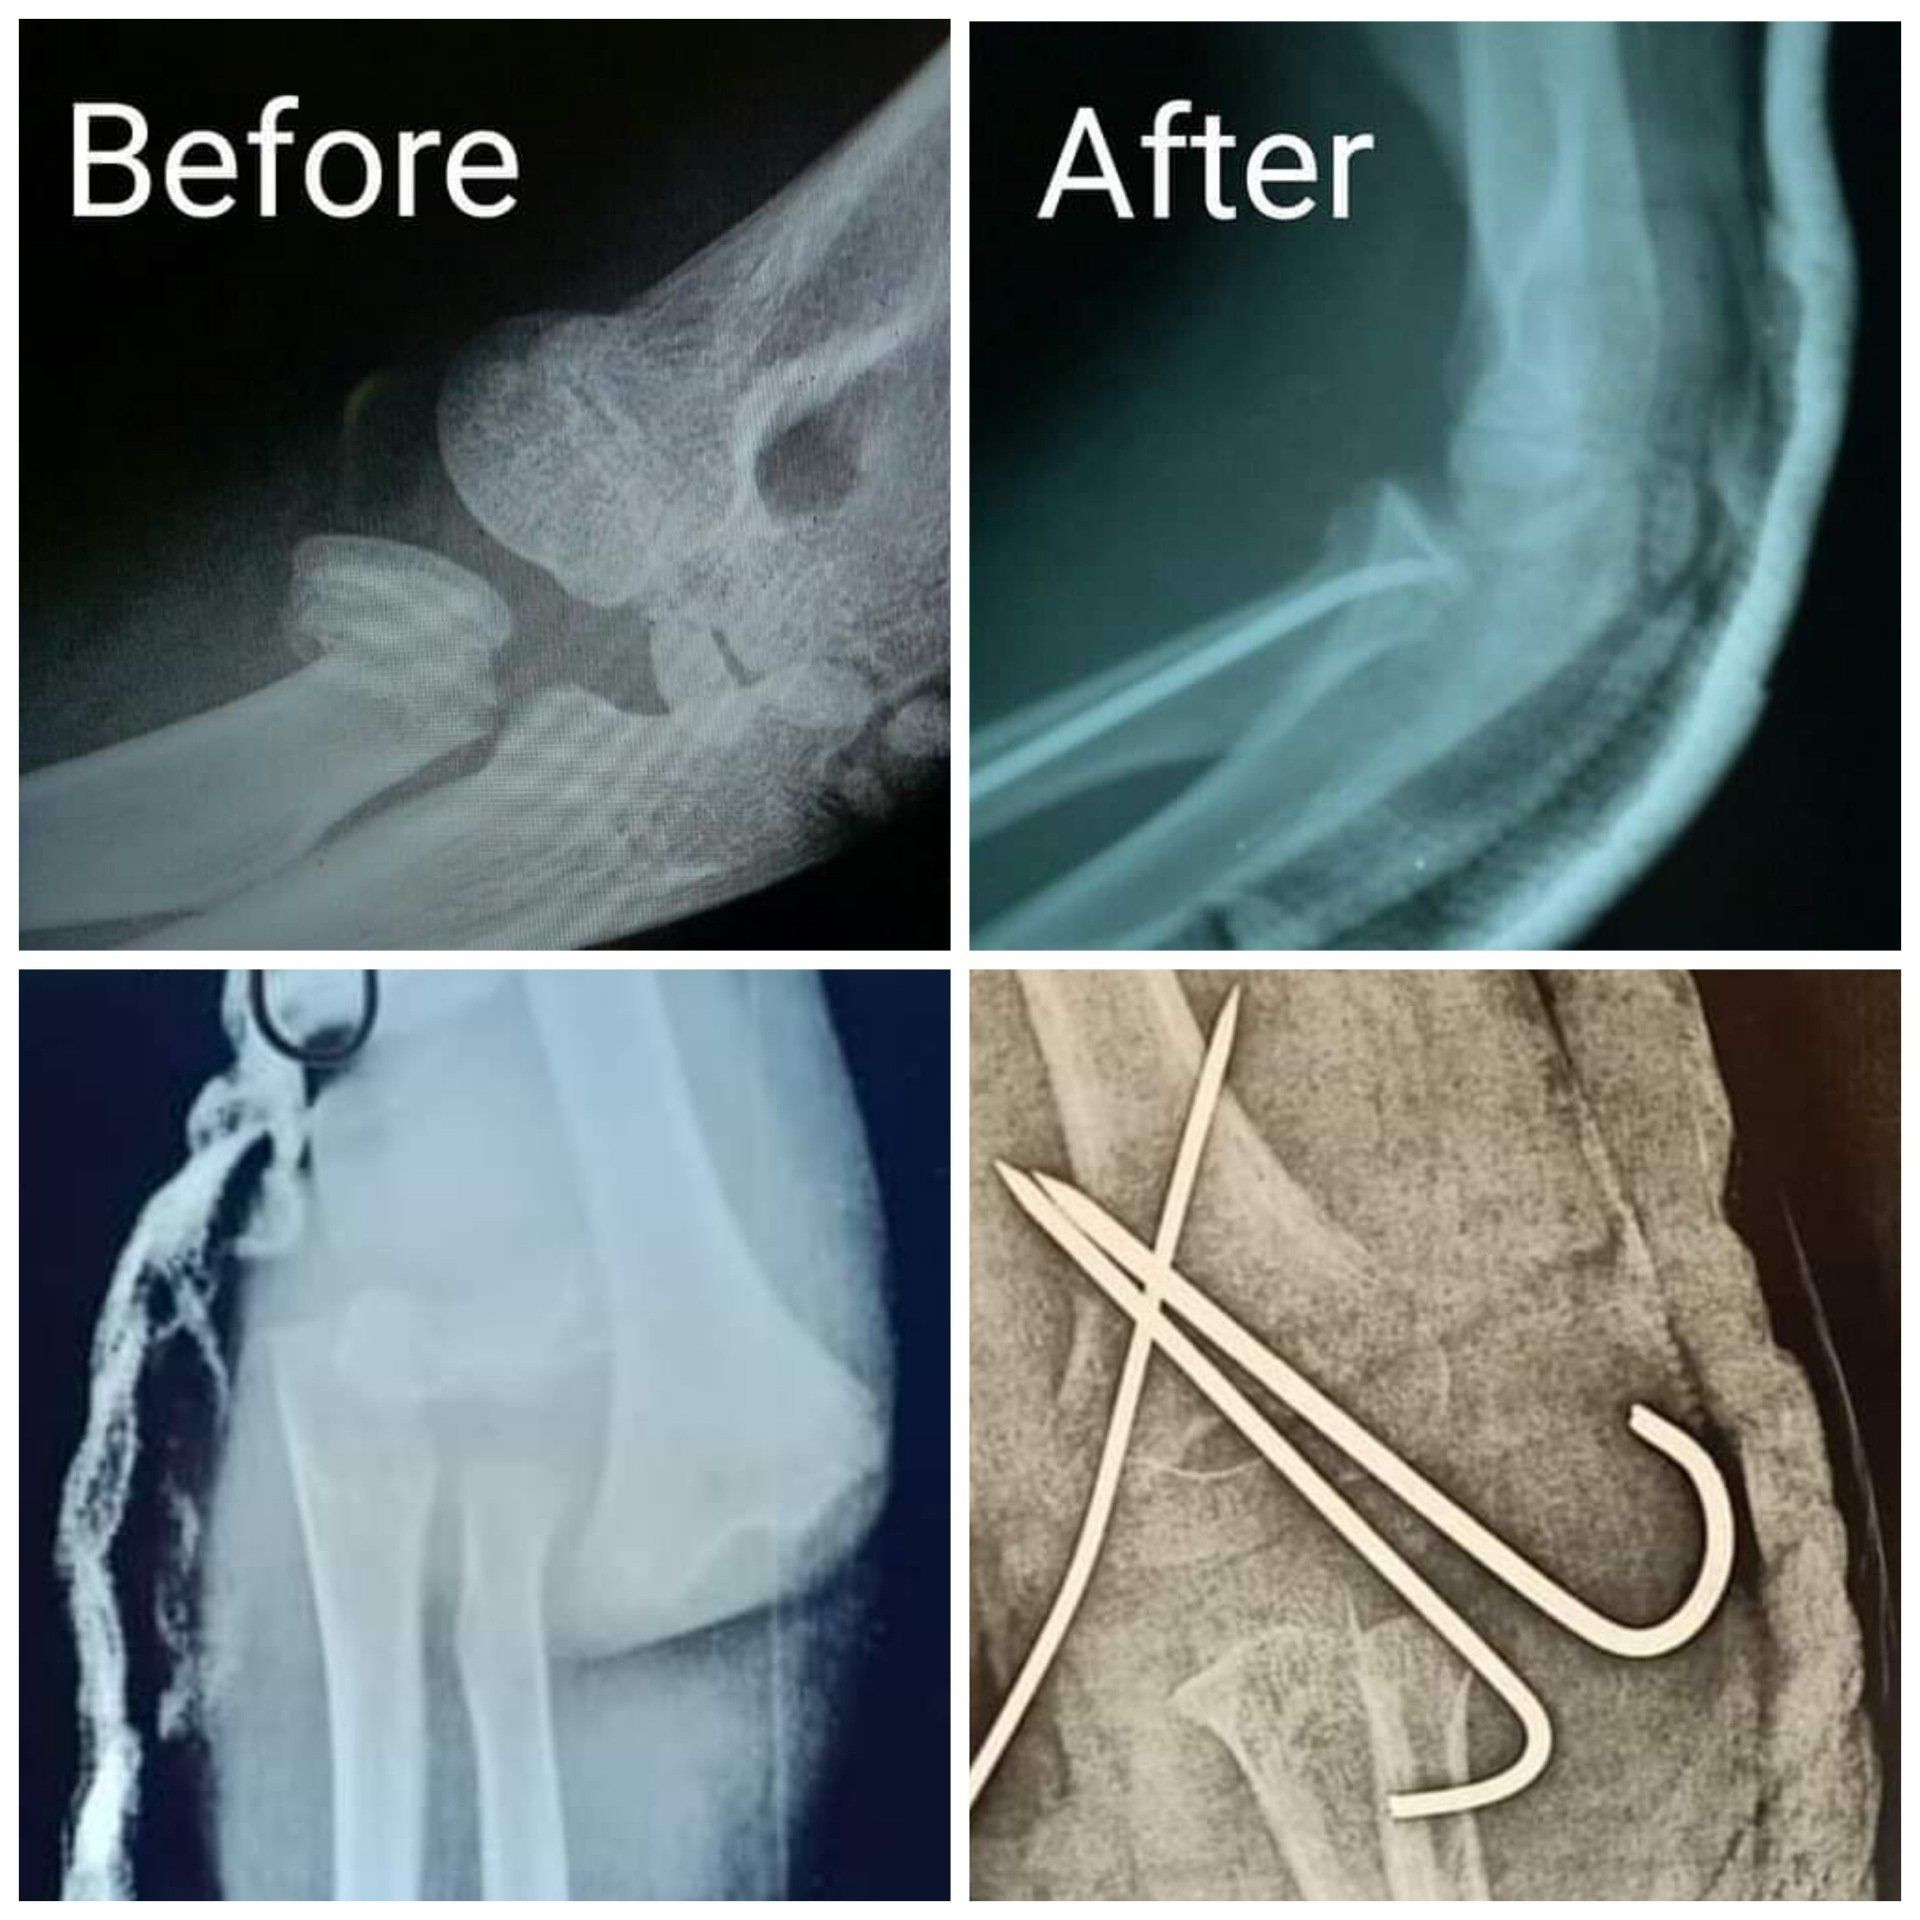

من حالاتنا